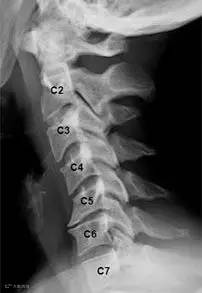

怎样才能知道自己的颈椎是否健康?日常生活中身体发出的小信号会提示不同类型的颈椎问题。

信号一:长时低头伏案工作,感觉到头晕难受,考虑为椎动脉型颈椎病;

信号二:不明原因的肩颈酸痛,手臂发麻,考虑为神经根型颈椎病;

信号三:正常直行走路却常出现“跑偏”问题,考虑为脊髓型颈椎病;

信号四:经常有不明原因的头晕、眼花、耳鸣、手麻、心动过速、心前区疼痛等一系列症状,考虑为交感神经型颈椎病。

如果同时出现上述几类症状,则考虑为混合型颈椎病。